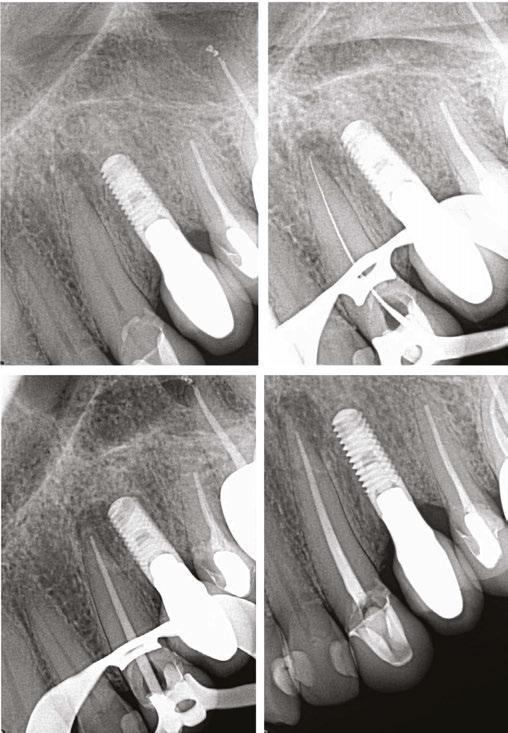

The Dynamic Navigation System (DNS) is a new technology in endodontics, and it is like a GPS for the handpiece and the drill.5 DNS has a more straightforward workflow (Figure 1) and is less time-consuming than static navigation.6 Previous studies revealed DNS’s high accuracy and efficiency for EMS.7 DNS enables the surgeon to deliver a minimally invasive EMS. Its high accuracy allows endodontists to conduct EMS in more difficult cases, such as areas with no direct visualization and close to vital anatomical structures. To date, DNS has been explored for different EMS steps, including bone window,8 osteotomy, and

root-end resection (RER).9 DNS can improve the accuracy and efficiency of EMS performed both by novice and experienced endodontists.10

DNS has numerous components. The main components include a central console, a display for the user interface, a section in the upper part containing motion-tracking cameras, and a lighting system, which varies from manufacturer to manufacturer (Figure 2). The cameras identify the DNS trackers that are attached to the patient’s face and to the handpiece and create a precise 3D model of the surgical site and the handpiece’s relation to the site regarding the angle, spatial position, and drilling depth.5

To plan for DNS surgery, the cone beam computed tomography (CBCT) Digital Imaging and Communications in Medicine (DICOM) file is directly uploaded into the DNS software. A key advantage of the DNS is that it does not require separate software to open and visualize the CBCT scan. Once the CBCT scan DICOM file is in the DNS software, the surgeon can plan the EMS procedure. After surgical planning, the DNS software requires a calibration step, in which the software recognizes the trackers attached to the handpiece and the patient’s dentition and memorizes their geometry to ensure that the handpiece and the drill are accurately represented on the planned drilling path. It has been suggested that the pre-surgical steps should not take more than a total of 15 minutes.6 After calibration, the DNS software becomes live for navigation, guiding the user to the drill at the correct angle and position. The DNS software guides drilling in real-time, and when the desired depth is reached, the DNS software indicates to stop, and the procedure is completed.

DNS has a learning curve like other technologies. It is crucial to undergo thorough training before treating a patient although the DNS is easy to operate, which makes the DNS learning curve less steep. A relatively low number of trial attempts are sufficient to calibrate the operator on DNS prior to the surgery.11 A previous study showed that after 20 trial attempts, both novice and experienced endodontists delivered EMS more accurately and efficiently than freehand.5 Overall, the DNS has a less challenging learning curve and is easy to fit into the surgeon’s existing EMS workflow.

Figures 1A-1F: X-Guide workflow. 1A. X-Clip fit. 1B. CBCT scan. 1C. Surgical planning. 1D. DNS trackers calibration. 1E. System check. 1F. Live navigation screen

Figures 2A-2D: DNS trackers for the X-Guide software (X-Nav Techologies, Lansdale, Pennsylvania). 2A. Handpiece tracker assembled. 2B. Patient’s tracker attached to the X-Clip. 2C. X-guide system. 2D. Tracking camera using violet light

Figures 3A-3F: Root-end resection using DNS (X-Guide software). 3A. Live navigation for the linear cuts. 3B-3D. Live navigation screen representation over the axial, coronal, and sagittal CBCT scan plans. 3E. Ultrasonic tip (P1B, Helse Ultrasonics, SP, Brazil). 3F. DNS 3D- live navigation

EMS involves many steps, including osteotomy, root-end resection, root-end cavity preparation, and root-end filling.14 All these steps are crucial for EMS success.15 Each EMS step can be a source of error, and cumulative errors can ultimately impact the EMS outcome and longevity of the tooth. To date, DNS has been mainly explored for osteotomy, bone-window cut, and root-end resection.8,9,10,12,13 Previous studies have demonstrated the high accuracy and efficiency of DNS for osteotomy and root-end resection.9,16 Most of these studies indicated 2D- and 3D-deviation metrics below or close to 2 mm.10,12 Moreover, these studies also showed a lesser root-end resection angle compared to freehand surgery.9

Bone window or “bony lid” surgery was introduced in 1987 for direct surgical access to the apical root of mandibular molars for root-end resection16 (Figure 4). It is an alternative surgical method to conventional osteotomy using burs or drills. The procedure involves preparing and removing a bone window, which is then reinserted into its original position after the surgery. One advantage of bone window surgery is that it preserves and maintains bone that would have been removed by conventional osteotomy with burs (Figure 4). The bone window works as an autogenous graft without substitute materials for guided tissue regeneration providing essential bone remodeling factors, including osteoinductive molecules, proper scaffolding, and osteogenic cells.18,19

Recently, DNS was successfully applied for a bone-window surgery8 study which was the first to integrate X-Guide software into a piezoelectric device for bone window cutting in EMS (Figure 5). The authors showed that DNS improved the accuracy and efficiency of EMS piezosurgery. Piezosurgery’s many advantages include the ability to perform minimally invasive procedures, preserve neurovasular structures, control bleeding, and reduce thermal damage.23,24 The piezosurgery preserves more of the cancellous properties and more osteocytes than traditional osteotomy.22 Moreover, piezosurgery offers less edema, less trismus, reduced pain, and improved quality of life after the surgery.23

Figures 4A-4C: Bone window cut with DNS. 4A. Linear cuts for the bone window using Ultrasonic tip (P1B, Helse Ultrasonics, SP, Brazil). 4B. Bone window. 4C. Distal root-end resection following the bone window

Figures 5A-5B: DNS Live screen for the bone window cut. 5A. Representation of the straight-cutting alignment and guidance on bone window procedure. 5B. 3D pre-surgical planning for bone window cut